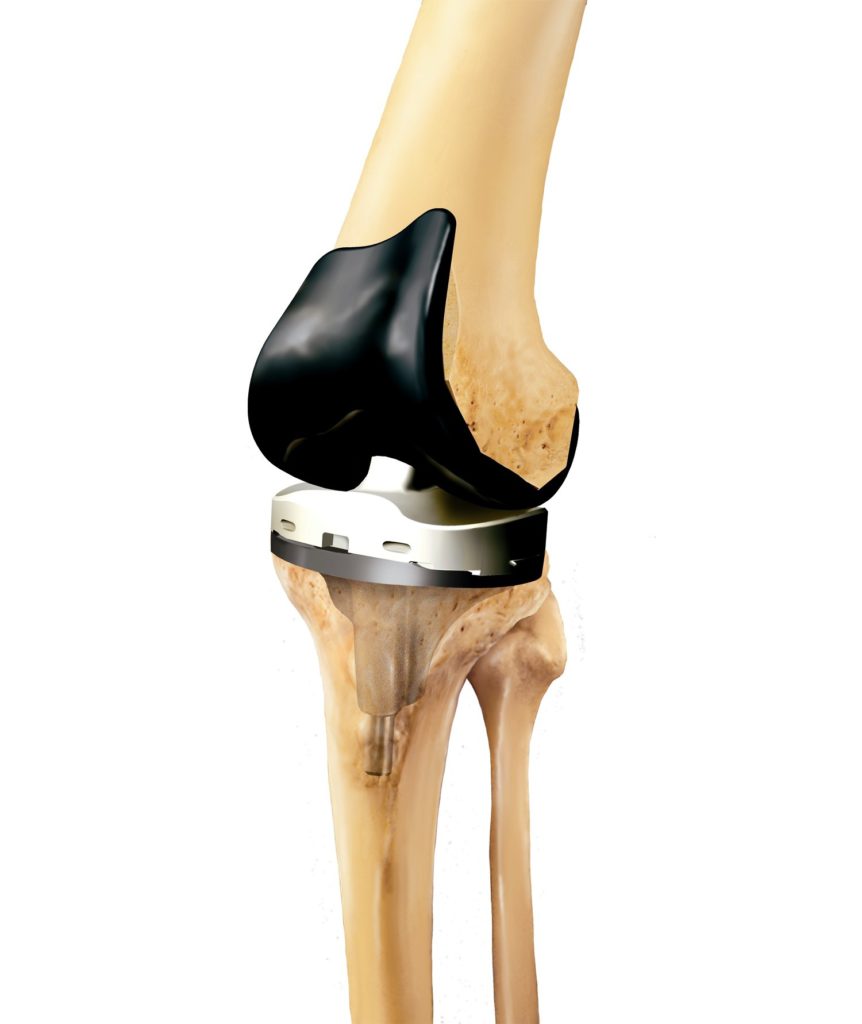

При полном эндопротезировании замене подлежат все три отсека, при частичном – только один из них. Большинство искусственных имплантатов состоят из четырех компонентов:

- Большеберцовый компонент. Плоский элемент, закрепляемый к верхней части голени. Изготавливается в виде металлической платформы с полиэтиленовой (пластиковой) вставкой. Материалом для изготовления — мягкий металл, например, титановый сплав.

- Бедренный компонент – крупная, изогнутая часть имплантата, закрепляемая в бедренной кости. Изготавливается из металла или керамики, чаще из прочных сплавов кобальта и хрома, потому что эта часть участвует в большинстве движений.

- Коленный компонент – куполообразная часть, заменяющая поврежденную коленную чашечку, трущуюся о бедренную кость. Используется не при всех видах суставной хирургии, изготавливается из полиэтилена (прочного пластика).

- Пластиковая прокладка. Располагается между большеберцовой и бедренной частью. Изготавливается из пластика (полиэтилена). Эта гибкая распорка обеспечивает гладкую, скользящую поверхность для обновленного коленного сустава, позволяет ему изгибаться и гнуться.